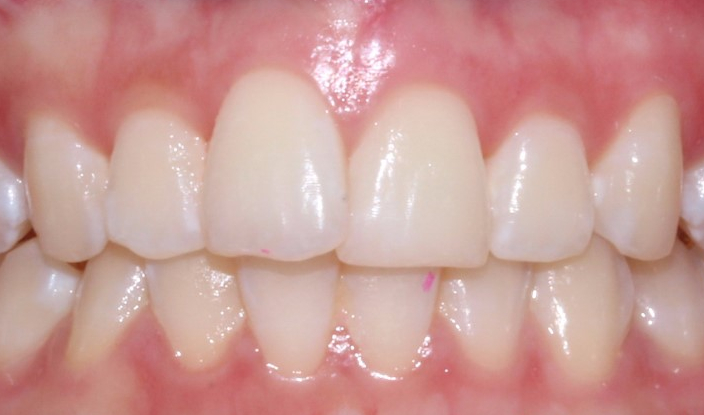

환자분의 상태는

상악 중절치와

앞니 절단연의 울퉁불퉁거림이

있는 편이어서

그 부분을 중점으로 치료하며

전체적인 배열에 맞게

2D교정 장치로

진행하기로 하였습니다.

불균형한 절단연의 원인은

불규칙한 치아배열로 인한 마모나

음식 등의 외부적인 요인이

있습니다.

절단연을 연마하는 것만으로도

심미적으로 굉장히 차이 나기 때문에

환자분의 요청에 따라

치아에 손상이 가지 않는

한도 내에서 심미성을 위해

조정 도와드렸습니다.